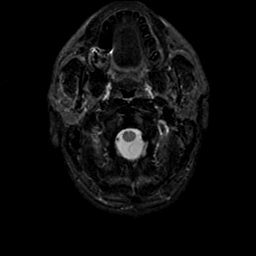

MR Study #9, April 14, 1991 -- Slice #1